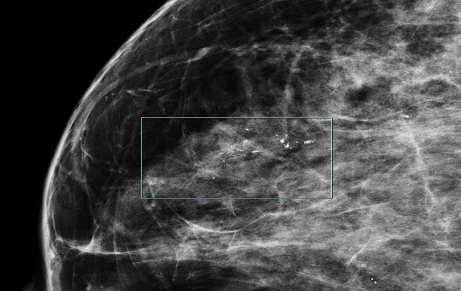

유방 미세석회화는 유방 조직 내에 칼슘 성분이 미세하게 침착된 현상을 말합니다. 이러한 석회화는 보통 크기가 매우 작아 육안으로는 확인이 불가능하며, 유방촬영술(mammography)을 통해서만 발견됩니다. 미세석회화는 대부분 증상이 없어 건강검진이나 유방촬영에서 우연히 발견되는 경우가 많습니다.

악성 미세석회화의 특징

악성 미세석회화는 다음과 같은 특징을 보입니다.

- 크기가 작고 미세함

- 불규칙한 모양과 크기

- 군집성(5개 이상이 한 곳에 모여 있는 형태)

- 선형 또는 분지형 배열

- 시간이 지남에 따라 수와 분포의 변화가 있음

이러한 특징을 가진 미세석회화는 유방암 또는 전암성 병변과 연관될 가능성이 높습니다. 특히 비침윤성 유관암(DCIS)이나 침윤성 유관암의 초기 단계에서 이러한 형태의 미세석회화가 자주 관찰됩니다. 따라서 이러한 소견이 보이면 추가 조직검사와 적절한 치료가 필요합니다.